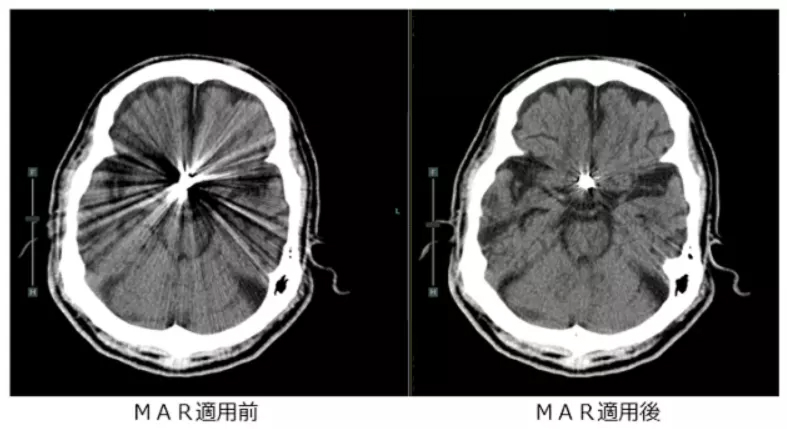

- 金属アーチファクト低減(MAR)技術により、手術等で体内に挿入した金属の影響でCT検査上見えにくかった臓器の評価ができるようになりました。また血管内に留置したステント内の評価にも役立ちます。

頭部領域における撮影

くも膜下出血や脳梗塞など緊急性を要する脳血管疾患において、320列CT装置の強みである超高速撮影で検査することにより、短時間で画像診断を行うことができます。